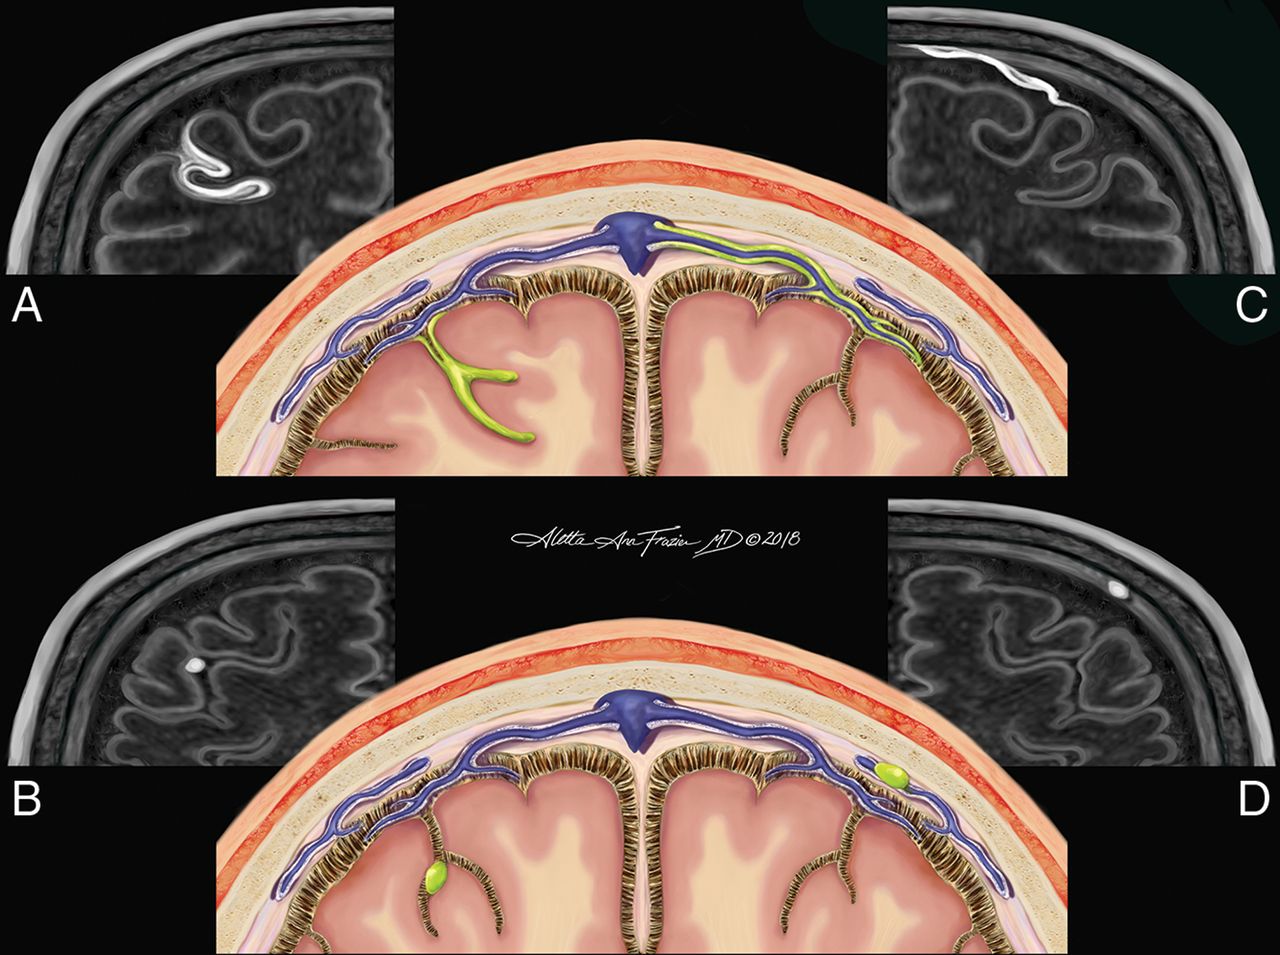

The magnetization-prepared FLAIR subtraction image, alongside the pre- and postcontrast magnetization-prepared FLAIR images, was reviewed by 2 independent raters (a postgraduate year 4 radiology resident and an academic MS neurologist) who were blinded to subject identity, disease state, and treatment regimen. Hyperintensities noted on the subtraction image were located on anatomic images and demarcated, if present, in the meningeal space on postcontrast images only. All foci were localized in 3 orthogonal planes before notation. When needed, coregistered MP2RAGE T1-weighted images were used for confirmation of anatomic locations. The pattern of enhancement was categorized on the basis of location and morphology and stratified into 1 of 4 subtypes. Subarachnoid spread/fill foci were characterized by the presence of contrast in the subarachnoid space distributed in an amorphous manner (Fig 1A). Subarachnoid nodular foci were characterized by small, round areas of contrast, usually 1–2 voxels (0.7–1.4 mm) and were adherent to the pial surface (Fig 1B). Vessel wall enhancement was characterized by contrast outlining the outer margin of a large meningeal vessel with a signal void in the lumen of the vessel, often resulting in a characteristic tram-track appearance (Fig 1C). Dural foci were characterized by discrete regions of enhancement clearly situated along the dural surface without extension into the subarachnoid space (Fig 1D). Following both independent reviews, a consensus review was performed under the supervision of an expert third rater (an academic neuroradiologist with 12 years of experience). After consensus review, follow-up images underwent linear registration (with 9 df) to baseline images. Consensus regions of contrast enhancement on baseline images were reviewed for their presence or absence on follow-up scans. The total number of foci per subject that persisted between scans was compared among different morphologies of meningeal enhancement and correlated with demographic and clinical data. Additionally, the proportion of baseline foci per subject that persisted to follow-up scans was also compared with morphologic, demographic, and clinical factors.

Original illustration depicting the 4 morphologies of meningeal enhancement seen in this analysis. Subarachnoid spread/fill pattern (represented by green in A) is an amorphous and ill-defined collection of contrast pooling within the cerebral sulci. The subarachnoid nodular pattern (B) is defined as a punctate, discrete site of meningeal enhancement located within the cerebral sulci abutting the pial surface. The vessel wall pattern (C) is characterized by extension of contrast along the outer margin of large meningeal vessels with a preserved internal flow void creating a characteristic tram-track appearance. The dural pattern (D) is a circumscribed, rounded focus of contrast situated along the dural margin without extension into the subarachnoid space. The perivascular, tubular white structures (seen in schematics A, B, and D) represent the recently discovered meningeal lymphatic system. Reaccumulation of leaked contrast from the CSF into these meningeal lymph channels is a potential mechanism for the venous rim pattern (C).